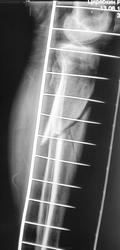

- https://radiomed.ru/sites/default/files/styles/case_slider_image/public/user/12/16.p2070032a.jpg?itok=laBMJHVK

красиво!!! DHSку теперь придется убрать, а вот что поставить? Ну может PFN, интрамедуллярный стержень с дополнительной фиксацией шейки. С б/берцовой проще, перелом благодатен для интрамедуллярного остеосинтеза.